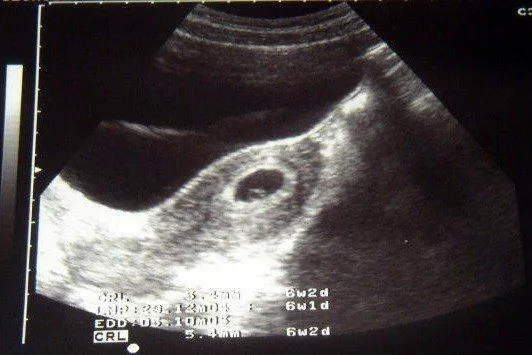

Imágenes de ecografías de 6 semanas

Explora nuestra galería de imágenes de ecografías de 6 semanas, ideales para ver el desarrollo temprano del embarazo y compartir con la familia.

eco 6 semanas (5) | Tener un bebé es facilisimo.

Imágenes de ecografías de 6 semanas - Imagui